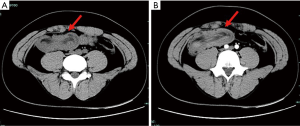

Case 4 was a 26-year-old man who presented to the emergency room with severe abdominal pain and bilious vomiting. Physical examination showed hyperactive bowel sounds and mild generalized abdominal tenderness without guarding or rigidity, but no rebound tenderness. Biological examination did not yield significant results; however, routine blood tests revealed a hemoglobin level of 128 g/L, and fecal occult blood was positive. CT revealed a large pedunculated mass with intussusception of the terminal ileum (Figure 4), and emergency laparotomy was subsequently performed. The invaginated segment was situated approximately 90 cm from the ileocecal valve, and there was an firm ovoid mass measuring 5 cm × 4 cm. The ileum, including the intussusception, was removed and primary side-to-side anastomosis was performed. Histopathology showed complete excision of the mass, which contained heterotopic pancreatic tissue. The patient was discharged home on postoperative day 8. The study was approved by the Ethics Committee of the First Affiliated Hospital, School of Medicine, Zhejiang University, China (No. 2020-93) and conducted in accordance with the Declaration of Helsinki (as revised in 2013). Written informed consent was obtained from the patients for publication of this manuscript and any accompanying images.